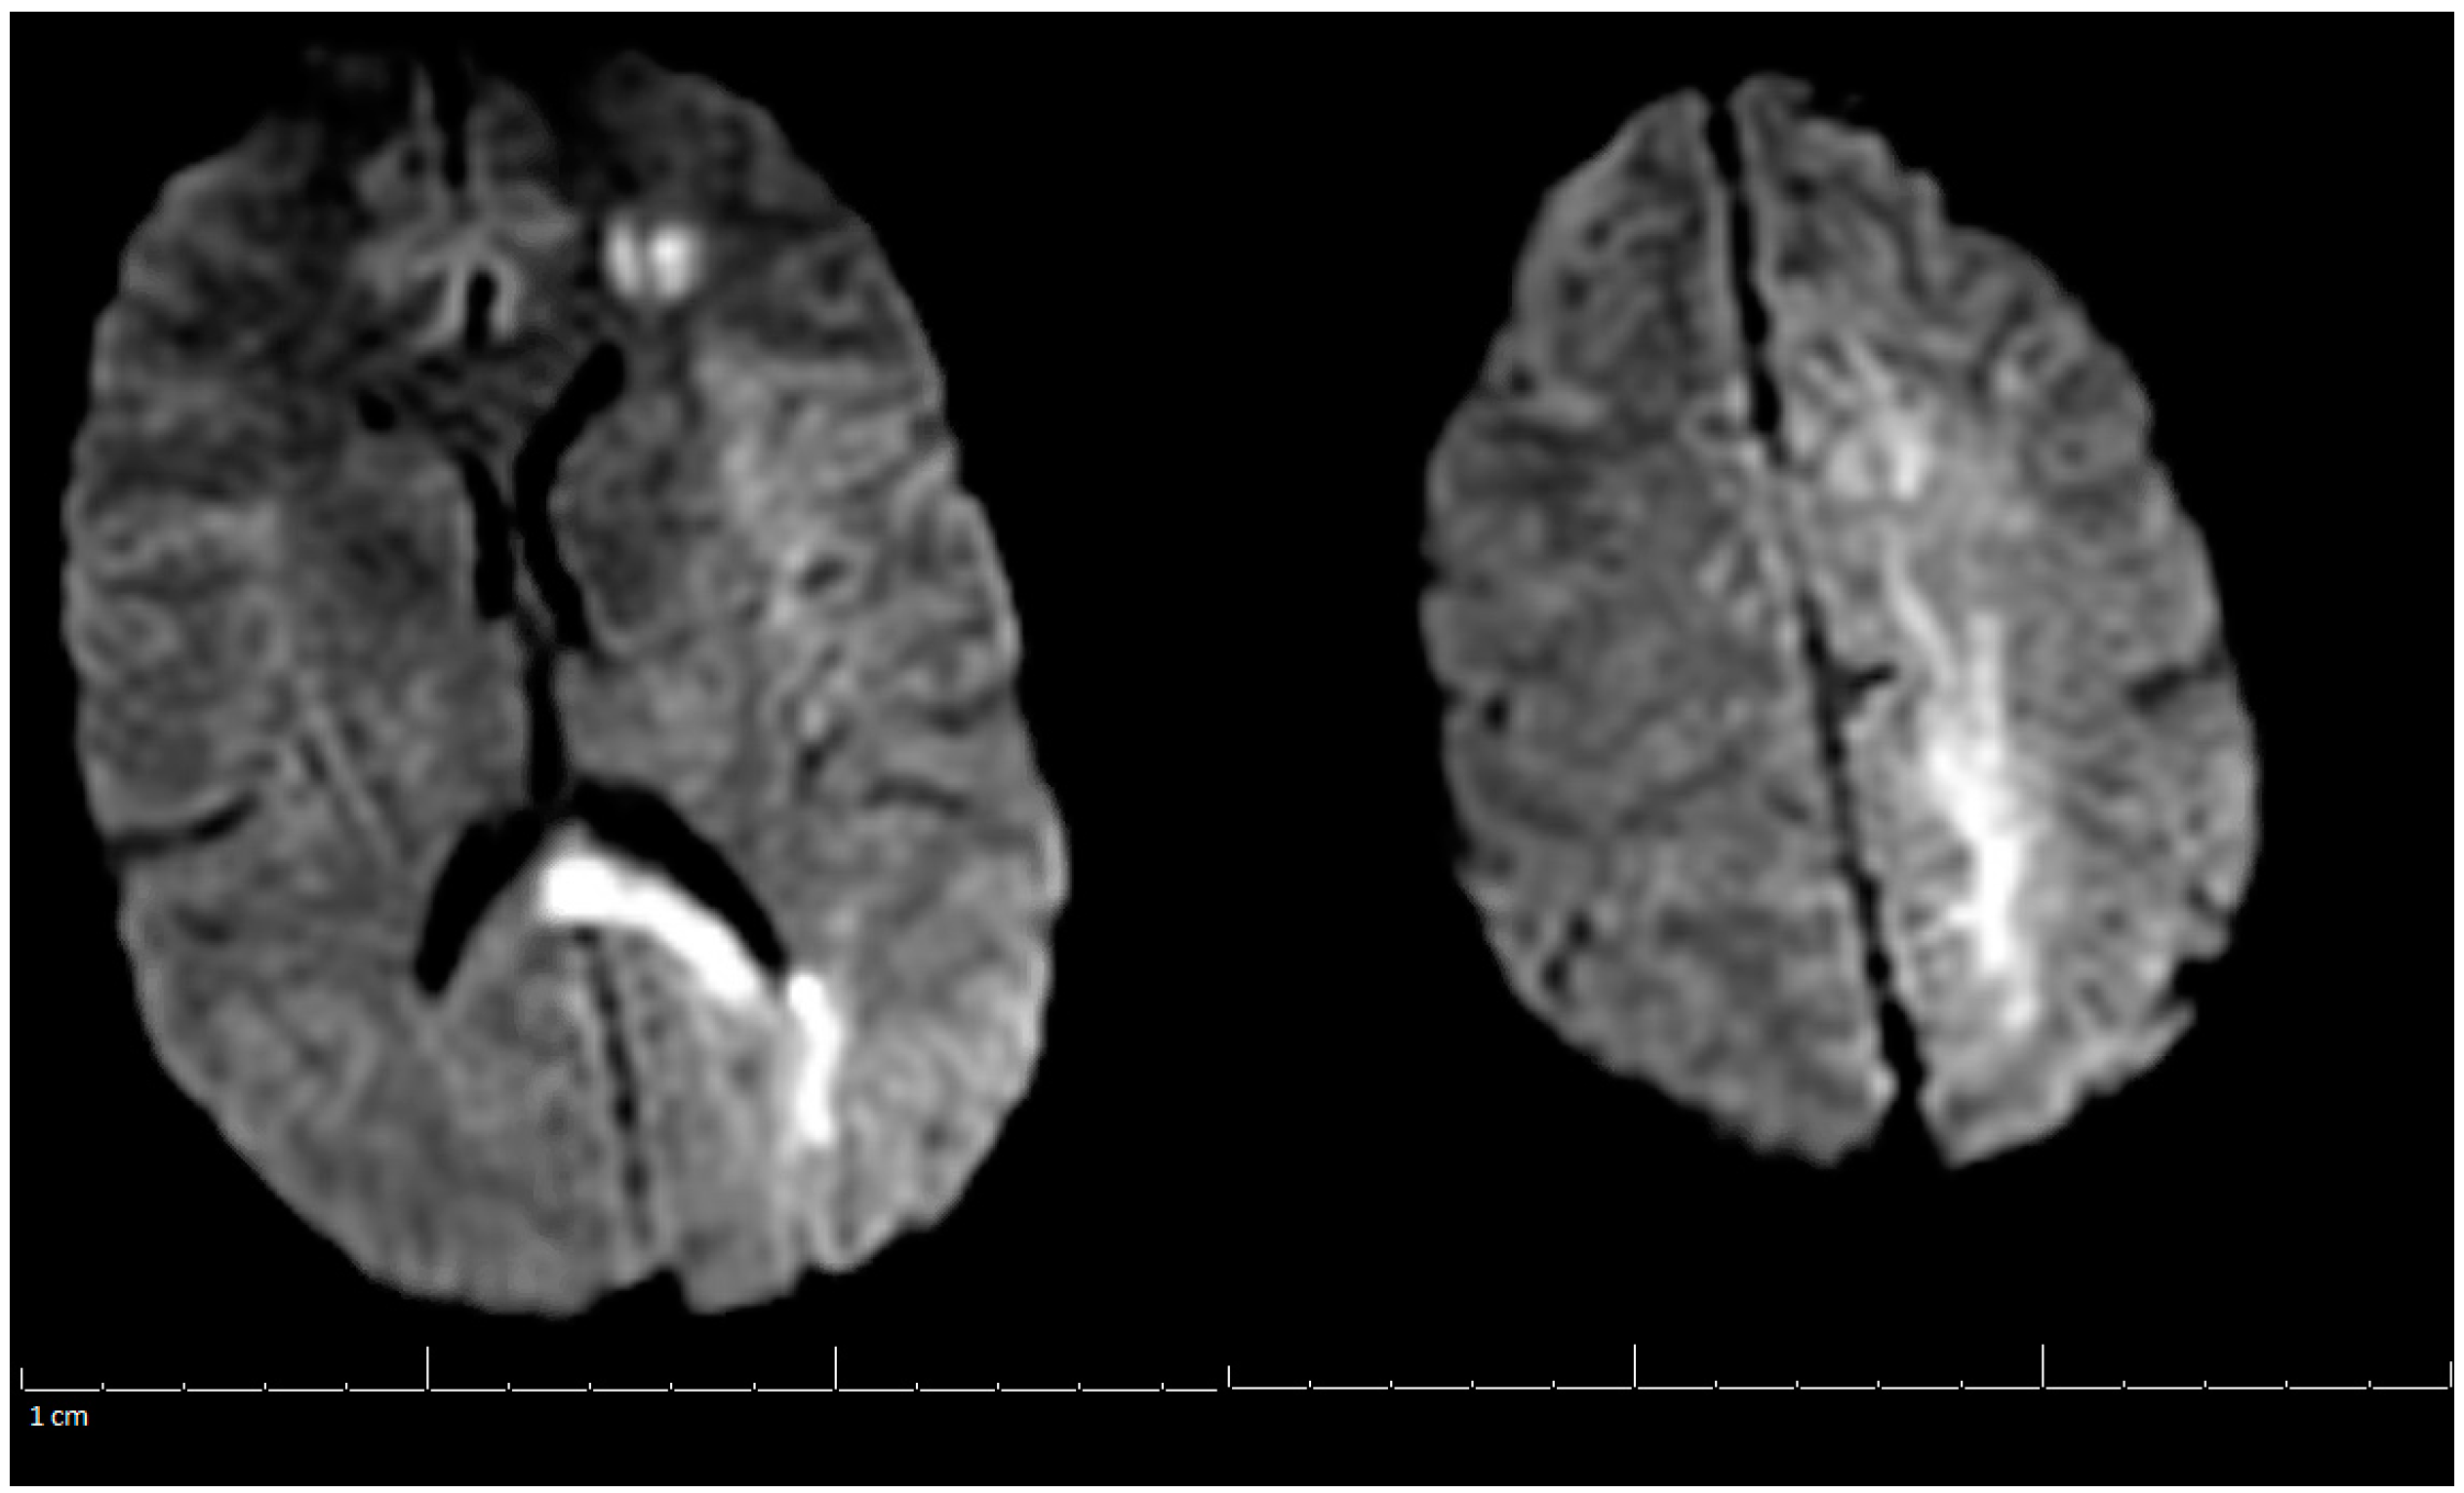

2. Case